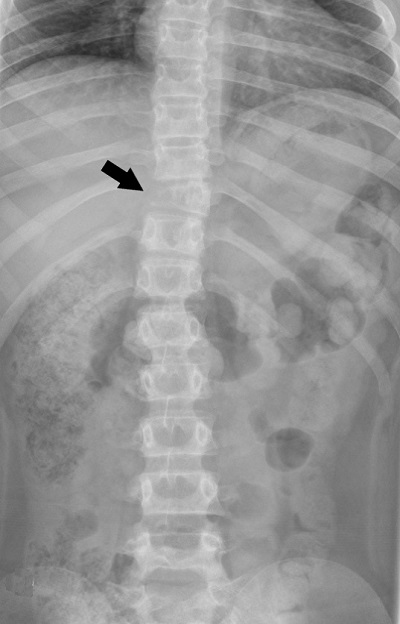

Ante una dorsalgia con datos de alarma (afectación neurológica) se realiza radiografía de columna vertebral (Fig. 1) que muestra una lesión lítica, expansiva, en pedículo derecho a nivel T10 y resonancia magnética (RM) de columna vertebral donde se aprecia una masa lobulada insuflante con cortical conservada pero adelgazada y nivel líquido en su interior en elementos posteriores de T10 que se introduce hacia el cuerpo vertebral, con componente epidural derecho que ocupa el 50-75% del canal medular y compresión medular con alteración de señal por mielopatía (desde nivel T8-T9 hasta cono medular), planteando el diagnóstico diferencial con lesiones tumorales de localización vertebral posterior, como son el osteoblastoma y el quiste óseo aneurismático (Fig. 2).

| Figura 2. RM de columna vertebral: masa lobulada insuflante en elementos posteriores de T10 que se introduce anteriormente hacia el cuerpo vertebral, rodeada de cortical ósea marcadamente adelgazada con múltiples niveles líquido-líquido junto con alteración de la señal de la musculatura paravertebral derecha por edema asociado (flechas). Asocia componente epidural en canal medular con compresión medular, ocupando el 50-75% de su totalidad |